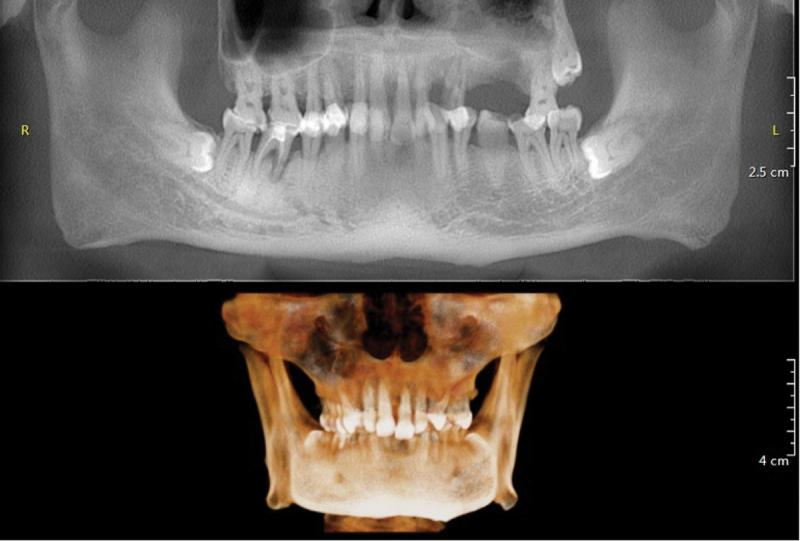

This case reports a 70-year-old male patient who developed an odontogenic brain abscess secondary to periodontal infection and underwent neurological surgery. Extract pus during surgery for the metagenomic next-generation sequencing (mNGS).

The mNGS of pus samples obtained from brain abscess aspiration identified the periodontal pathogens and . Consequently, he was referred to the department of stomatology for further examination and treatment.

本病例报告了一名70岁男性患者,因牙周感染继发牙源性脑脓肿并接受了神经外科手术。术中抽取脓液进行宏基因组下一代测序(mNGS)。

从脑脓肿穿刺抽取的脓液样本进行mNGS检测,鉴定出牙周病原体和。因此,他被转诊至口腔科进行进一步检查和治疗。